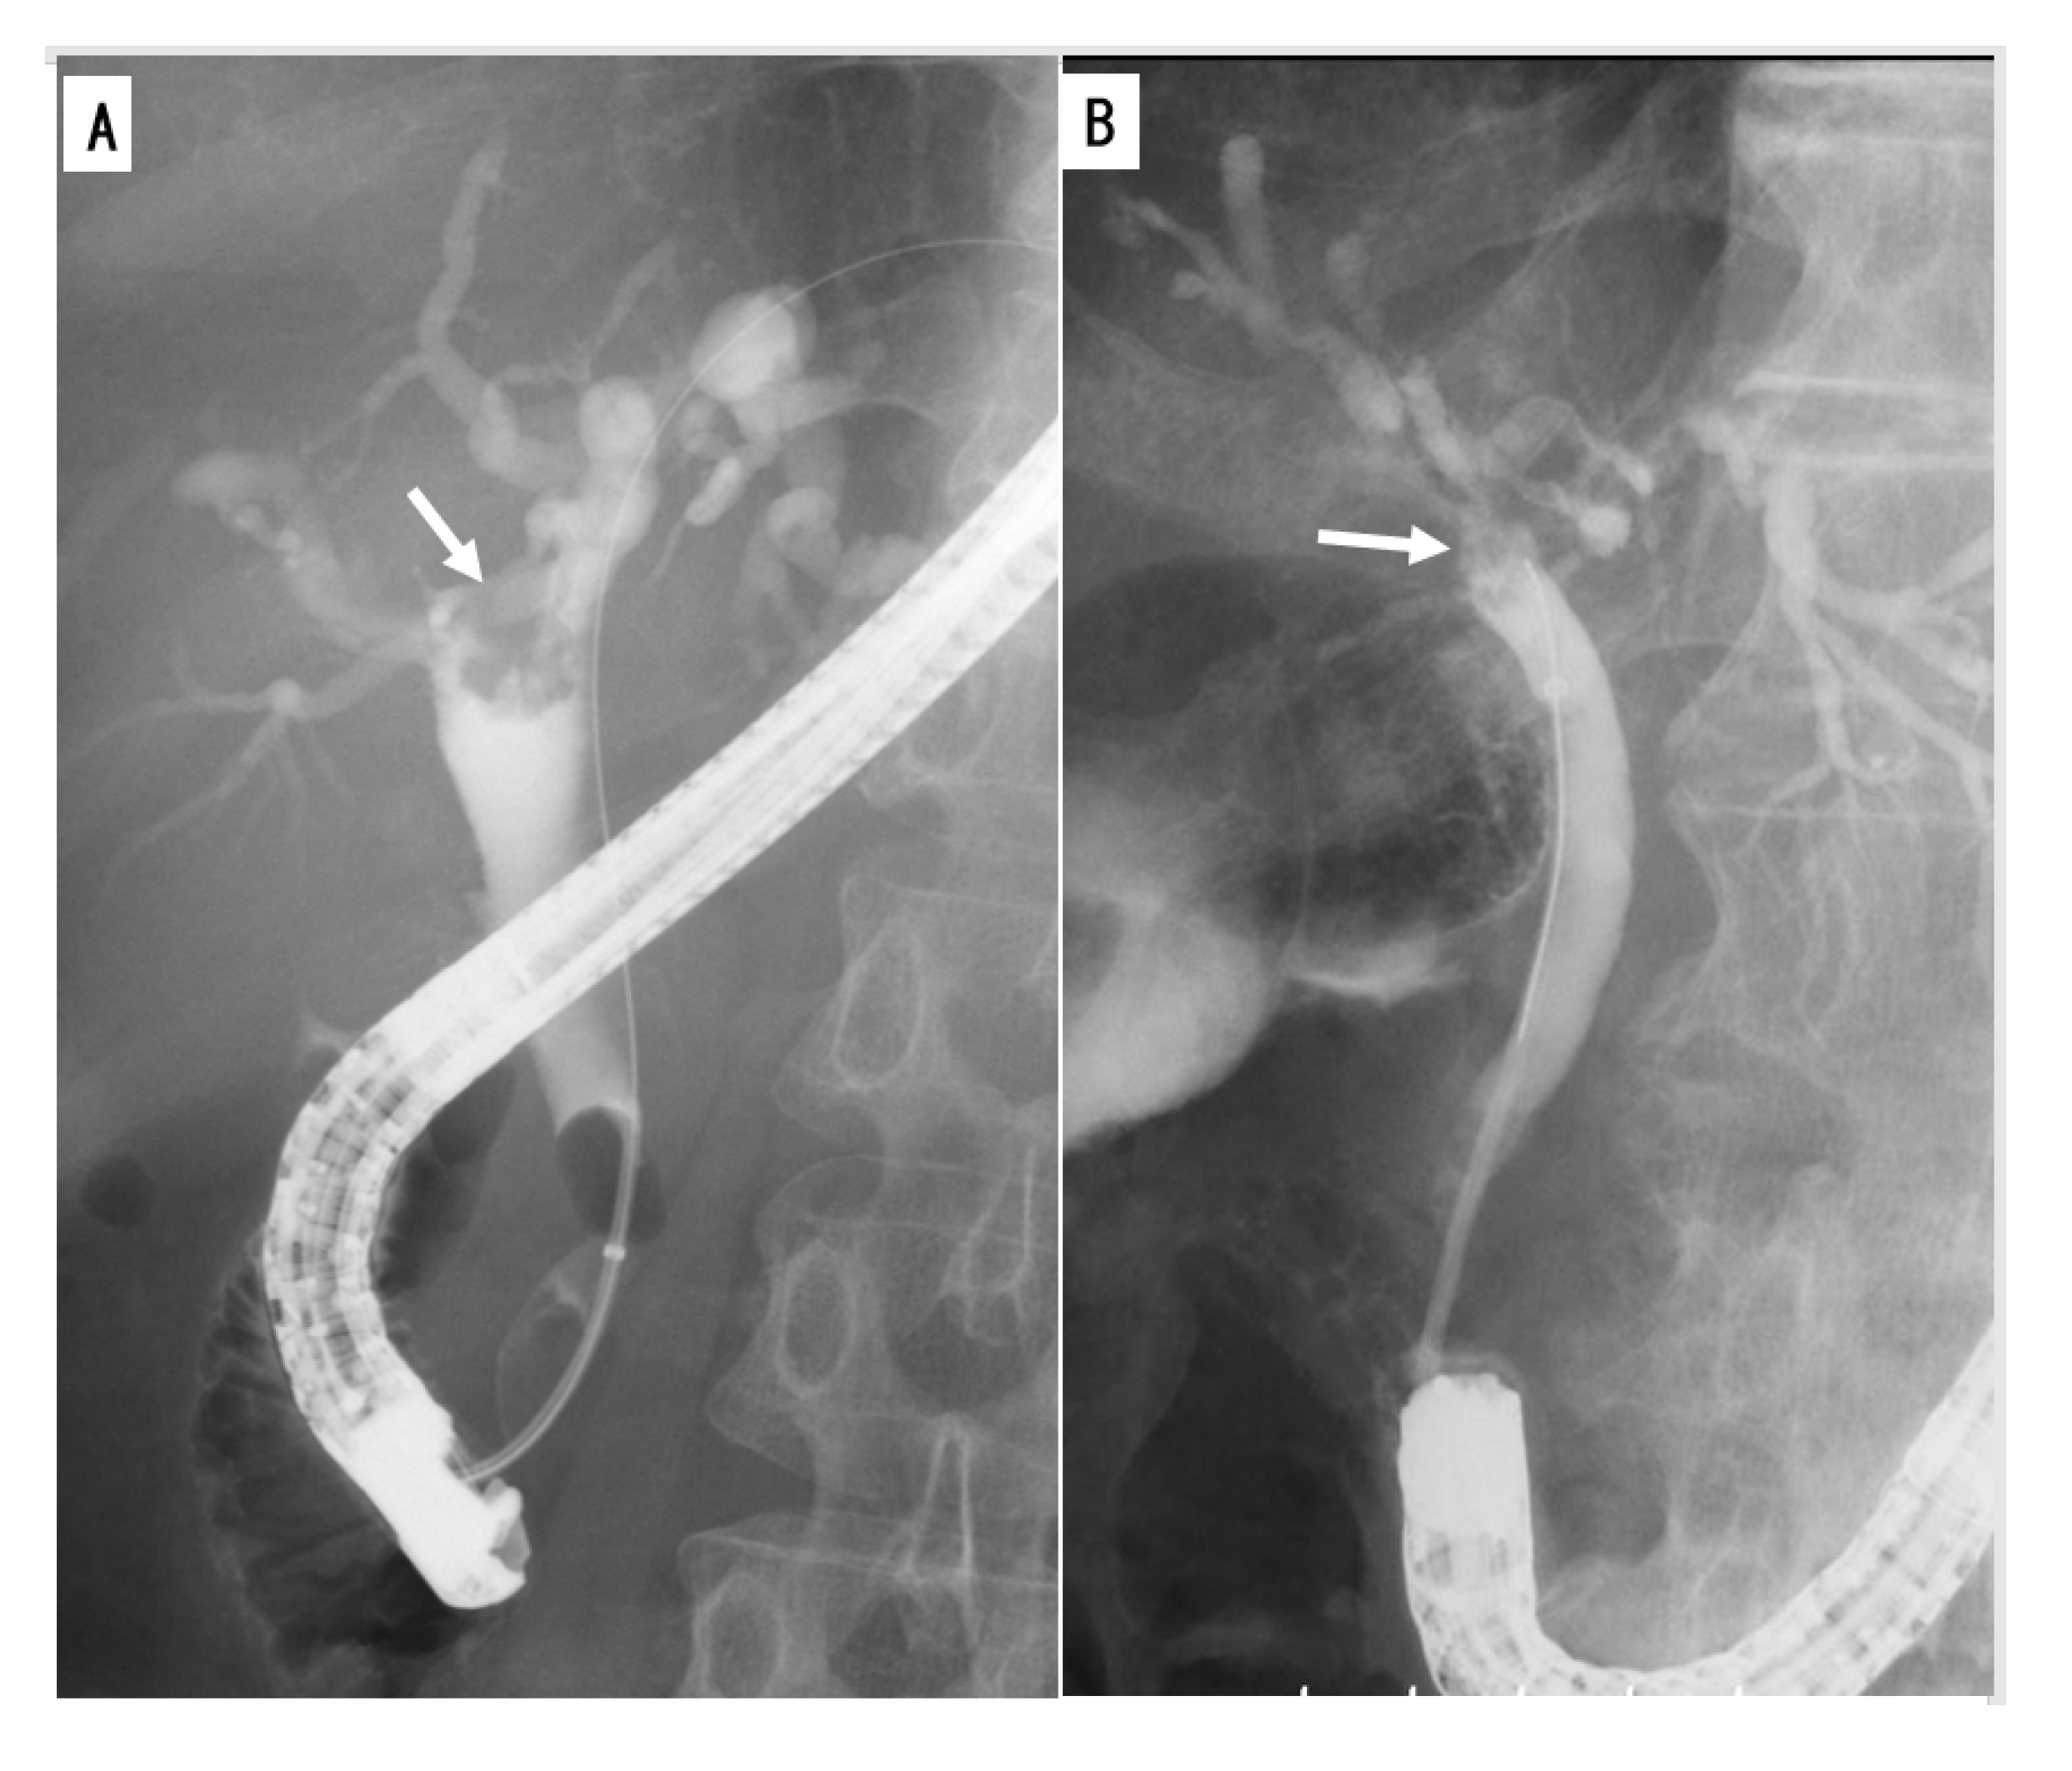

2.2.2. Cholangiography

- Yeh, T.S.; Tseng, J.H.; Chiu, C.T.; Liu, N.J.; Chen, T.C.; Jan, Y.Y.; Chen, M.F. Cholangiographic spectrum of intraductal papillary mucinous neoplasm of the bile ducts. Ann. Surg. 2006, 244, 248–253. [Google Scholar] [CrossRef] [PubMed]